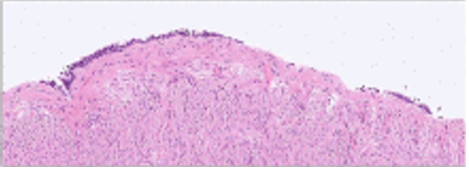

The pathology report revealed epithelial cells without mucin or cilia in the cyst surrounded by smooth muscle cells, compatible with a GDC (Figure 3).

Figure 3: The pathologic image revealed the Gartner’s duct cyst wall by non-ciliated, non-mucinous epithelial cells; a surrounding smooth muscle layer was evident.